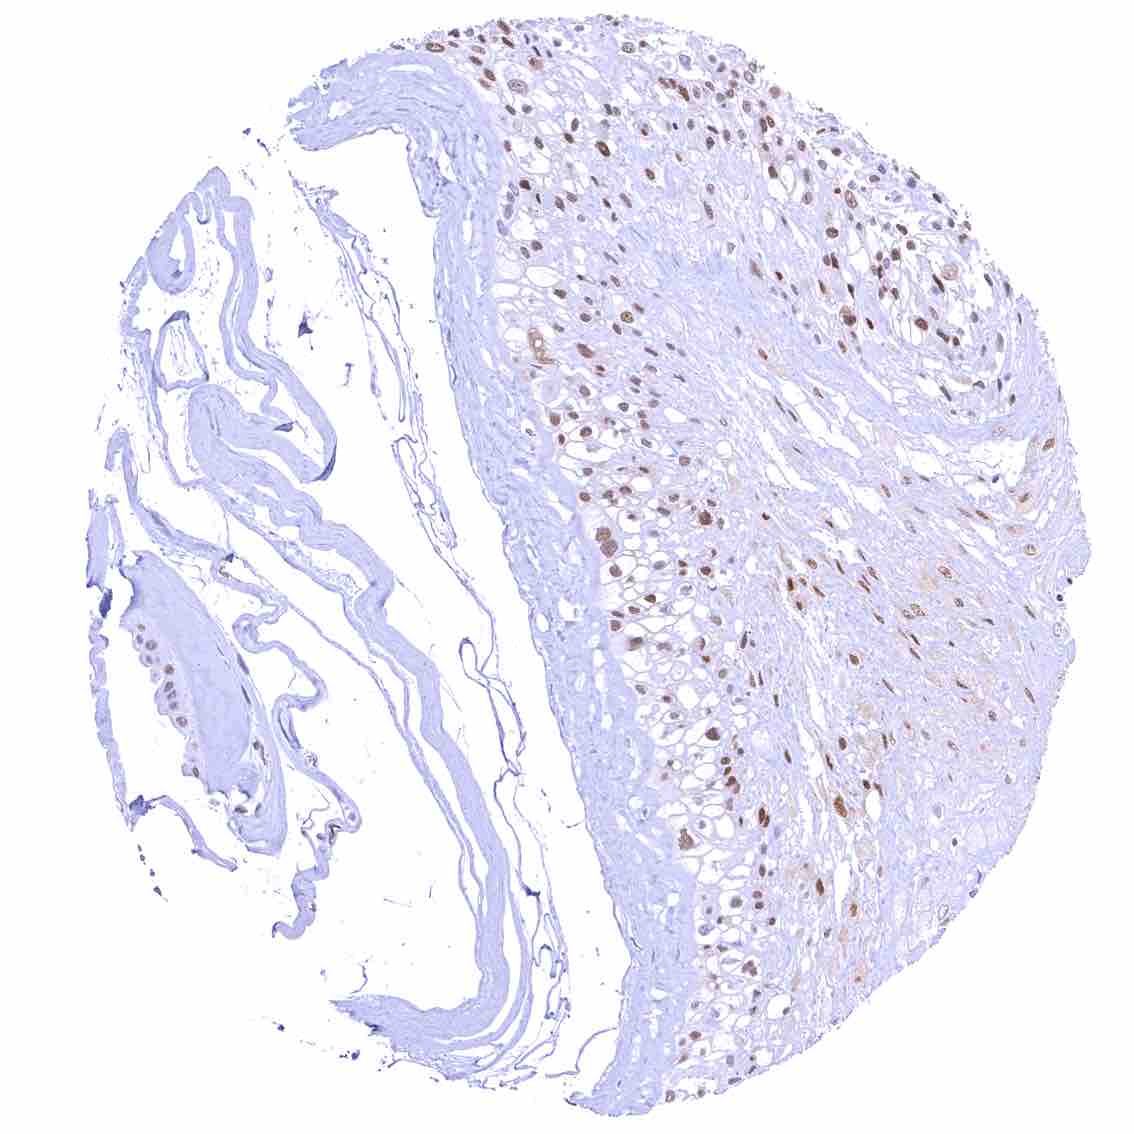

Skin – Moderate to strong nuclear p27 staining occurs in a large fraction of squamous epithelial cells and predominates in the more mature cell layers (top 50_ of the epidermis).

Skin, hairfollicel and sebaceous glands – Moderate to strong nuclear p27 staining in all cells of sebaceous glands. .jpeg